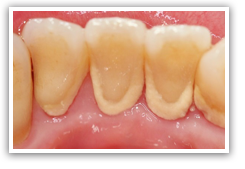

ほとんどの方はスケーリングとSRPで歯周病は改善、安定していくのですが、治療後も症状が改善しない、歯を失う可能性がある重度の歯周病の方は歯周外科と呼ばれる治療を行うことがあります。

歯ぐきをメスで切り、一度はがして中をむき出しにすることで、直視下にて歯石除去が可能になり、SRP後わずかに取り残した歯石も取りきることができます。

一度失ってしまった歯槽骨は大きな回復は期待できません。

しかし一部分に限局した歯周病であれば再生療法によって大幅な歯槽骨の回復を期待できます。

歯周外科を行う際に骨のなくなった部分にエムドゲインというコラーゲン繊維を填入すると、歯槽骨や歯根膜といった歯周組織に置き換えられていきます。